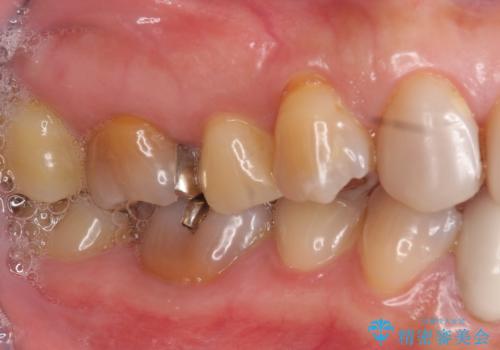

下顎は左側 4 番目から右側 4 番目までの 8 歯と左下 567 ブリッジをオールセラミッククラウンで補綴し、右下67の銀歯はセラミックインレーによる修復を行いました。

セラミックインレーについて

当院のセラミックインレーはemaxという強度と審美性に優れた材料を使用しています。

またプレス方式でインレーを製作しているため、削り出しで製作するCADCAMより優れた適合性も持ち合わせており、虫歯が再発しにくい修復物です。